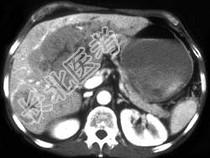

- 单项选择题女,67岁, 右上腹疼痛,消瘦四月余, CT检查如图,最可能的诊断为 ( )

A、肝囊肿

B、肝癌

C、肝脓肿

D、肝血管瘤

E、肝转移瘤